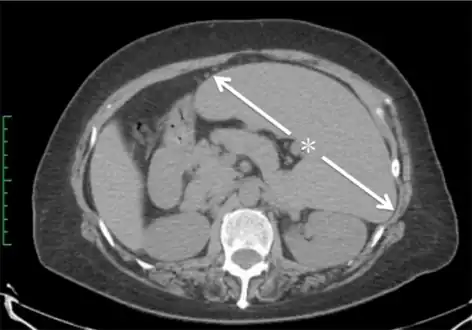

Computed tomography shows a massively enlarged spleen ( splenomegaly).

Abdominal CT is the most accurate and spleen need to be larger 2-3 times to be palpable below the costal margin in physical examination that can help in diagnosis.